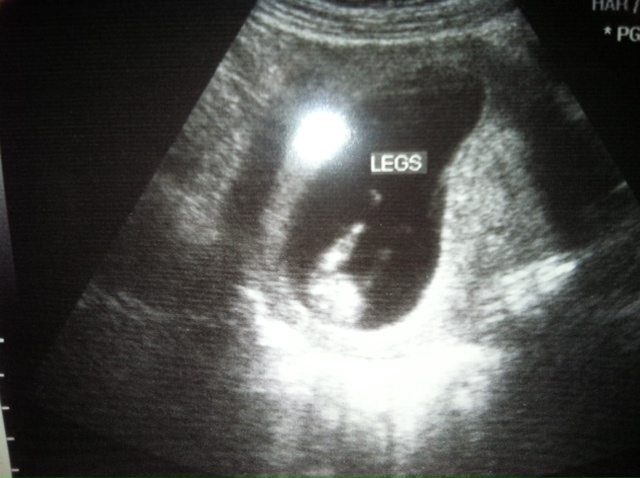

On week 12 at our second Dr.'s appointment we got our first ultrasound! The ultrasound wasn't originally planned, but the Dr. got us in for one because he was having trouble finding the heartbeat with the regular insturments. (yep, that was super nerve wracking) Turns out, our baby was moving around so much that it was very difficult to get a reading.

The ultrasound tech had no problem finding the baby. It was the heartbeat that ended up being difficult to measure, once again, because the baby was moving around like crazy.. kicking and moving all around. The baby was definately showing off for us. I could even feel the flutter of little kicks and was able to see them as they were happening on the big screen. It was an incredible experience.

Look at those long legs kicking up a storm. =) I am amazed at the detail we can already see at 12 weeks. I kept looking at the pictures off and on all day. I am amazed at this little miracle God has given us. We are truely blessed.